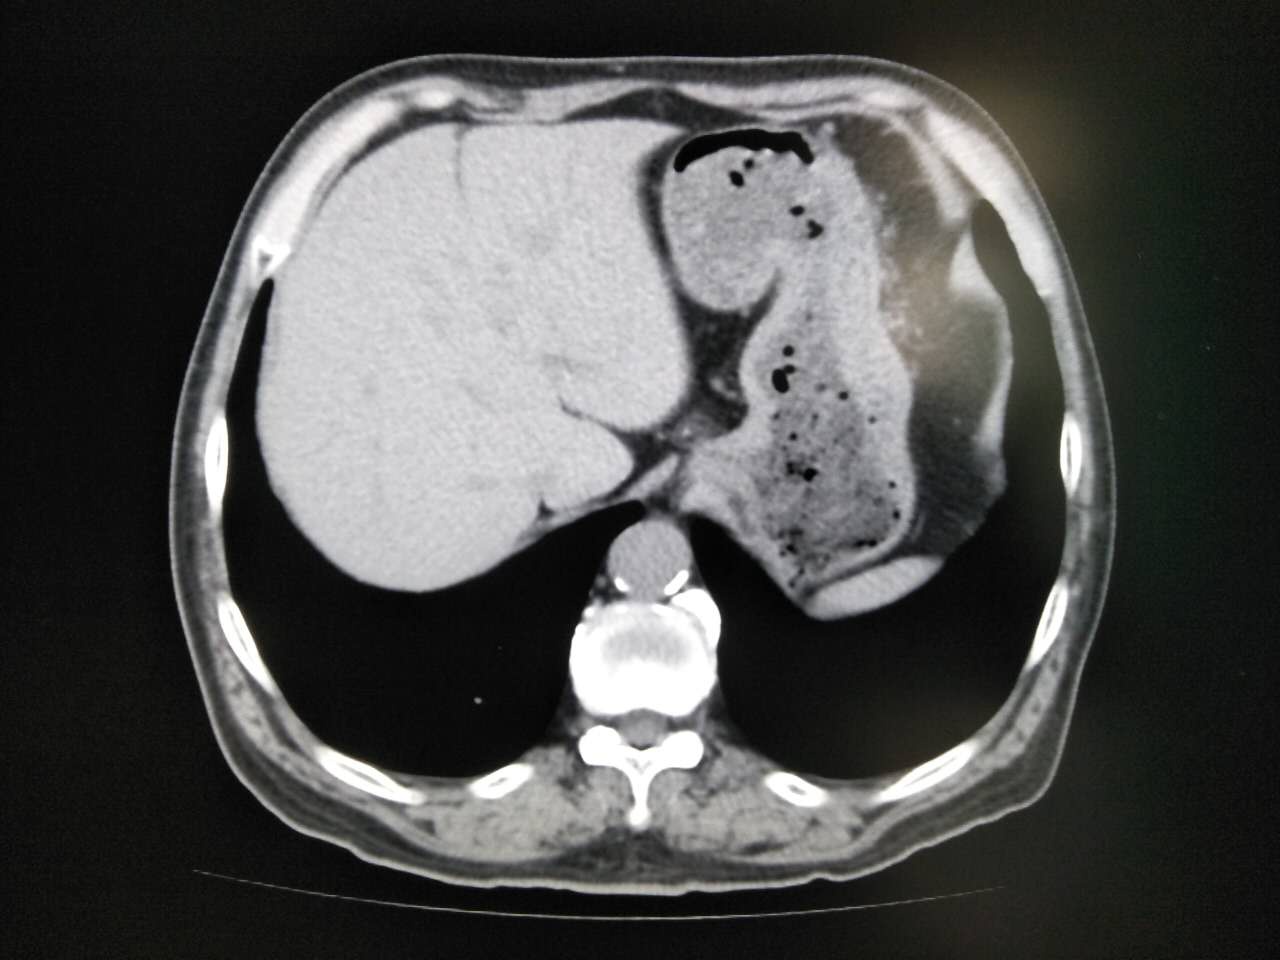

胃肠道CT 检查如要获得高质量的图像,肠道准备非常重要。如果小肠内有食物残渣, 就会影响肠腔的充盈与扩张,对于胃肠壁上较浅的病变难以显示。以下两例就是胃肠道未作准备,内容物较多,影响对比度,从而影响检查效果。

以下几例是胃肠道对比度较好的例子,可以清晰显示胃肠壁有无病变。